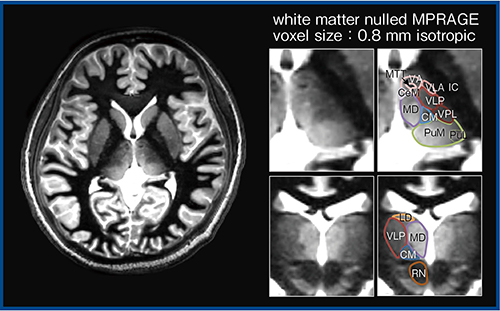

また,視床も認知特性に大きく影響する部分であり,特に脳卒中発症後の影響が大きいことがわかっている。脳卒中によって視床と海馬を接続する特定の神経線維が分断され,徐々に劣化することで,最終的に海馬に影響を及ぼすことが動物実験で明らかになった。この変化をヒトで見るためには,視床全体ではなく,視床核そのものの輪郭を特定する必要があるが,inversion time(TI)を短縮してコントラストを向上すれば描出が可能となる3),4)。次世代の3T MRIであるGalan ZGOでは,SNRが最適化され,個々の視床核の特定が可能となりつつある(図5)。7T MRIよりも高度な特定が可能であり,視床の解剖学的な組成を特定して,脳卒中発症後の変化を観察することができる。

図5 SNRを最適化したGalan ZGOによる視床核の輪郭特定(W.I.P.)